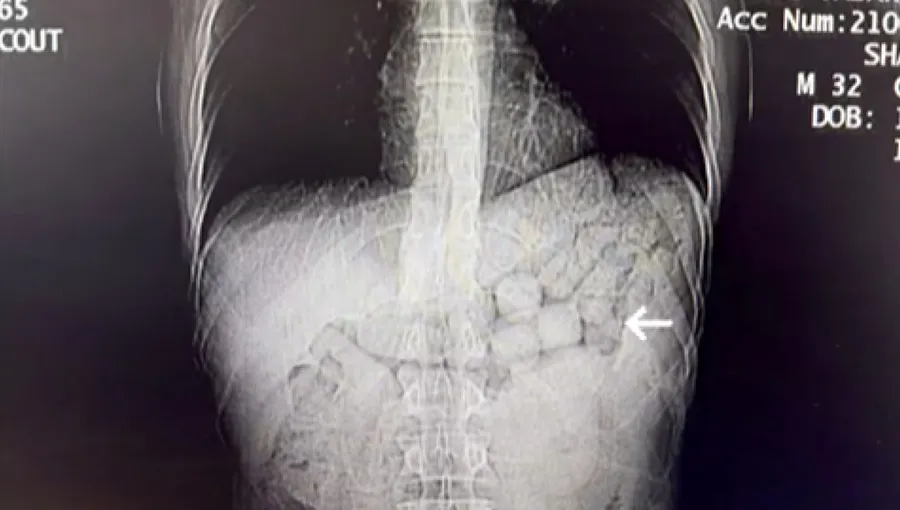

İl Emniyet Müdürlüğü Narkotik Suçlarla Mücadele Şube Müdürlüğü ekipleri, İran'dan Türkiye'ye farklı bir yöntemle uyuşturucu getirileceğini tespit etti. Diyarbakır otogarında takibe alınan İran uyruklu 2 şüpheli, 14 Ocak'ta düzenlenen operasyonla gözaltına alındı. Şüphelilerin yutma yöntemiyle uyuşturucu taşıdığı değerlendirilince, hastaneye sevk edildi.

Şüphelilerin çekilen tomografi görüntülerinde; mide ve bağırsak bölgelerinde yabancı cisimlere rastlandı. 3 gün süren kontrollerin ardından şüphelilerden, müdahaleyle 91 kapsül halinde 807,15 gram metamfetamin çıkarıldı. Emniyetteki işlemlerinin ardından adliyeye sevk edilen şüpheliler, çıkarıldıkları mahkemece tutuklandı.